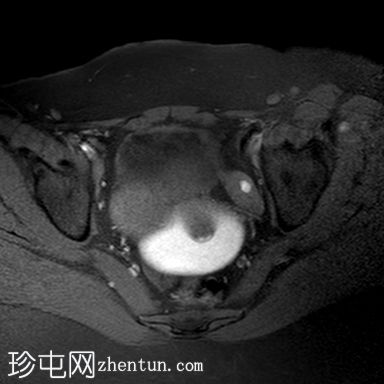

矢状位

T2加权像

阴道明显扩张,T1加权像呈中高信号,T2加权像呈高信号,耻骨联合下方可见一小局灶性隆起。

子宫大小正常,分区解剖结构正常。宫颈MRI表现正常。

右侧卵巢可见一圆形、边界清晰的囊肿,最大轴位径为4.2 x 4.3 cm,T1加权像呈低信号,T2加权像呈高信号。

左侧卵巢大小正常,可见一小出血性囊肿。

盆腔内可见少量游离液体。